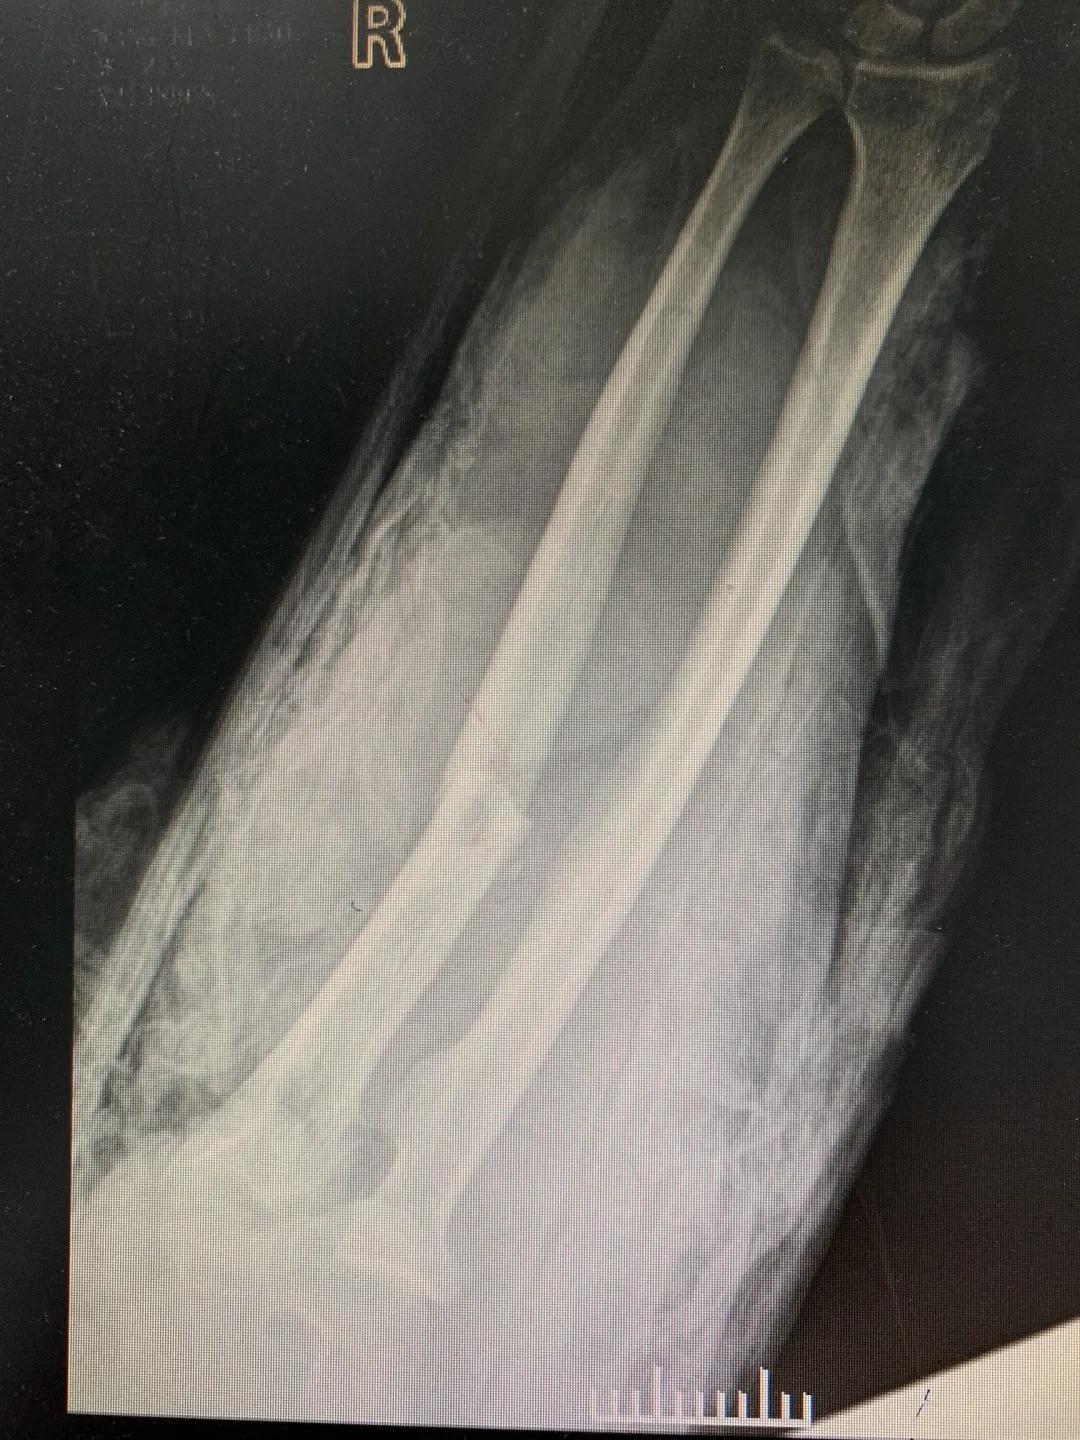

“正常的肢体都有皮肤保护着,如果没有皮肤,我们的肌肉、血管、神经、骨骼露在外面,都会发生坏死。”苑芳昌介绍,伤者的情况非常复杂,伴有多发骨折、肱骨骨折、骨关节的多发错位,还有腕部的骨折,更有血管、神经损伤。不仅如此,伤者右臂在机器里面受到绞伤,肌肉也已经大面积挫伤,各种复杂情形交织在一起甚至让手术“无从下手”。